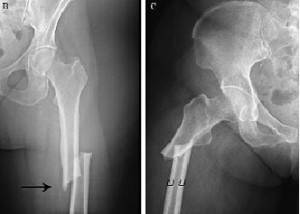

Este estudio contribuye a la escasa pero creciente literatura que asocia un número creciente de fármacos con osteonecrosis de la mandíbula relacionada con la medicación (ONMRM)  y subraya la importancia de considerar todos los fármacos posibles que elevan el riesgo de ONMRM de un paciente. Br J Clin Pharmacol, junio de 2021